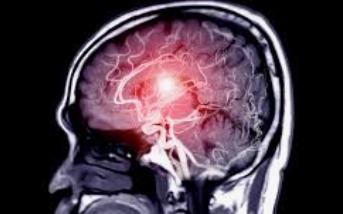

뇌졸중은 조기 발견하는 것이 무엇보다 중요합니다. 특히 특정 뇌졸중 전조증상이나 경고 징후는 뇌졸중이 일어나기 전에 충분히 알 수 있기 때문에, 이러한 징후를 알아두는 것은 생존율을 높이고 성공적인 치료 가능성을 높일 수 있습니다. 이 글은 이러한 뇌졸중 전조증상을 알아보고 조기 발견 및 즉각적인 조치를 위한 방법을 제공하는 것이 목표입니다.

뇌졸중은 뇌의 일부로 혈액 공급이 중단되거나 감소하여 뇌 조직의 산소와 영양분을 감소시키거나 없앨 때 발생합니다. 몇 분 안에 뇌 세포가 죽기 시작하기 때문에, 뇌졸중 전조증상을 알고 있는 것은 대응하는데 큰 도움이 됩니다. 뇌졸중은 크게 혈관이 막혀 발생하는 허혈성 뇌졸중과 혈관이 터져 발생하는 출혈성 뇌졸중의 두 가지로 분류할 수 있습니다.